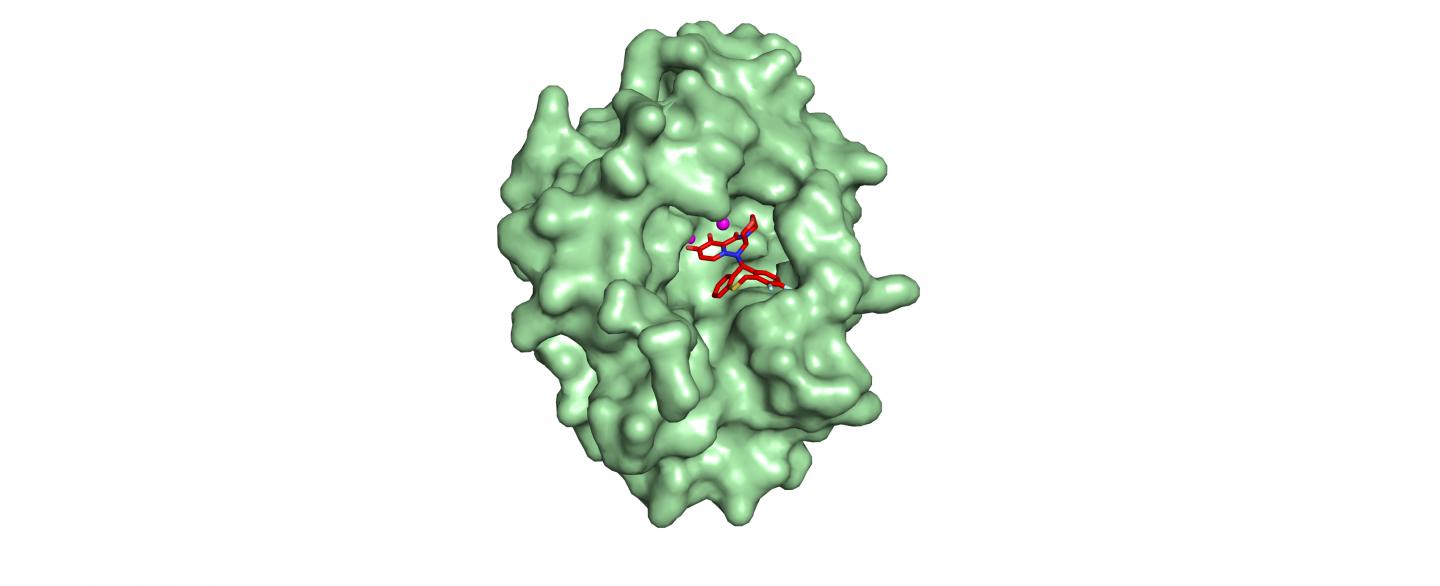

Flu’s response to new drug explored

Credit: Stephen Cusack, EMBL The new influenza drug Xofluza, developed by the Japanese pharmaceutical company Shionogi, was approved for clinical...